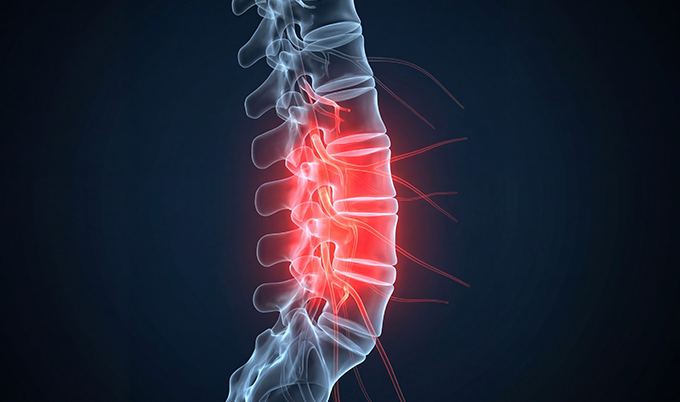

Research shows 95% of lumbar disc herniations occur at L4-L5 or L5-S1. These lower levels carry the highest loads and experience the most movement stress.

Herniated discs appear as bulging material protruding beyond normal disc boundaries. The inner nucleus pulposus pushes through tears in the outer annulus fibrosus on lumbar MRI for sciatica images.

This creates the pressure that compresses nerve roots causing your symptoms. Lumbar MRI for sciatica classifies herniation severity using standardized terminology that guides treatment.

Bulge: The entire disc circumference extends beyond vertebral edges but the outer wall remains intact. These often improve with conservative care alone.

Protrusion: Disc material pushes through a focal area but remains connected to the main disc. This is the most common finding on lumbar MRI for sciatica.

Extrusion: Disc material breaks through the outer wall and separates from the disc. These cause more severe compression requiring intervention.

Sequestration: Disc fragments migrate away from the original herniation site. These often require surgical removal for symptom resolution.

The scan shows disc height loss indicating degeneration throughout your spine. Dark signal intensity on T2-weighted images reveals disc desiccation.

This is loss of water content that normally cushions vertebrae. Studies show disc degeneration affects 98% of patients with lumbar herniations.

Lumbar MRI for sciatica also detects Modic changes – signal abnormalities in vertebrae adjacent to degenerated discs. Type 1 changes show bone marrow edema correlating with active inflammation and pain intensity.

Type 2 changes show fatty infiltration indicating chronic degeneration. These findings help predict which patients respond better to specific treatments.